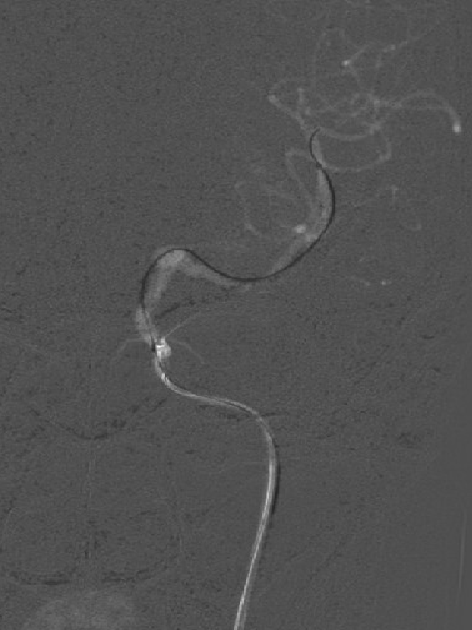

手术过程微导管到位:

Pipeline™ Flex 血流导向密网支架

Pipeline™ Flex 血流导向密网支架于密网支架充分打开,所以从外缘向内缘回拉,让密网支架位于血管中轴。

Pipeline™ Flex 血流导向密网支架密网支架充分打开。